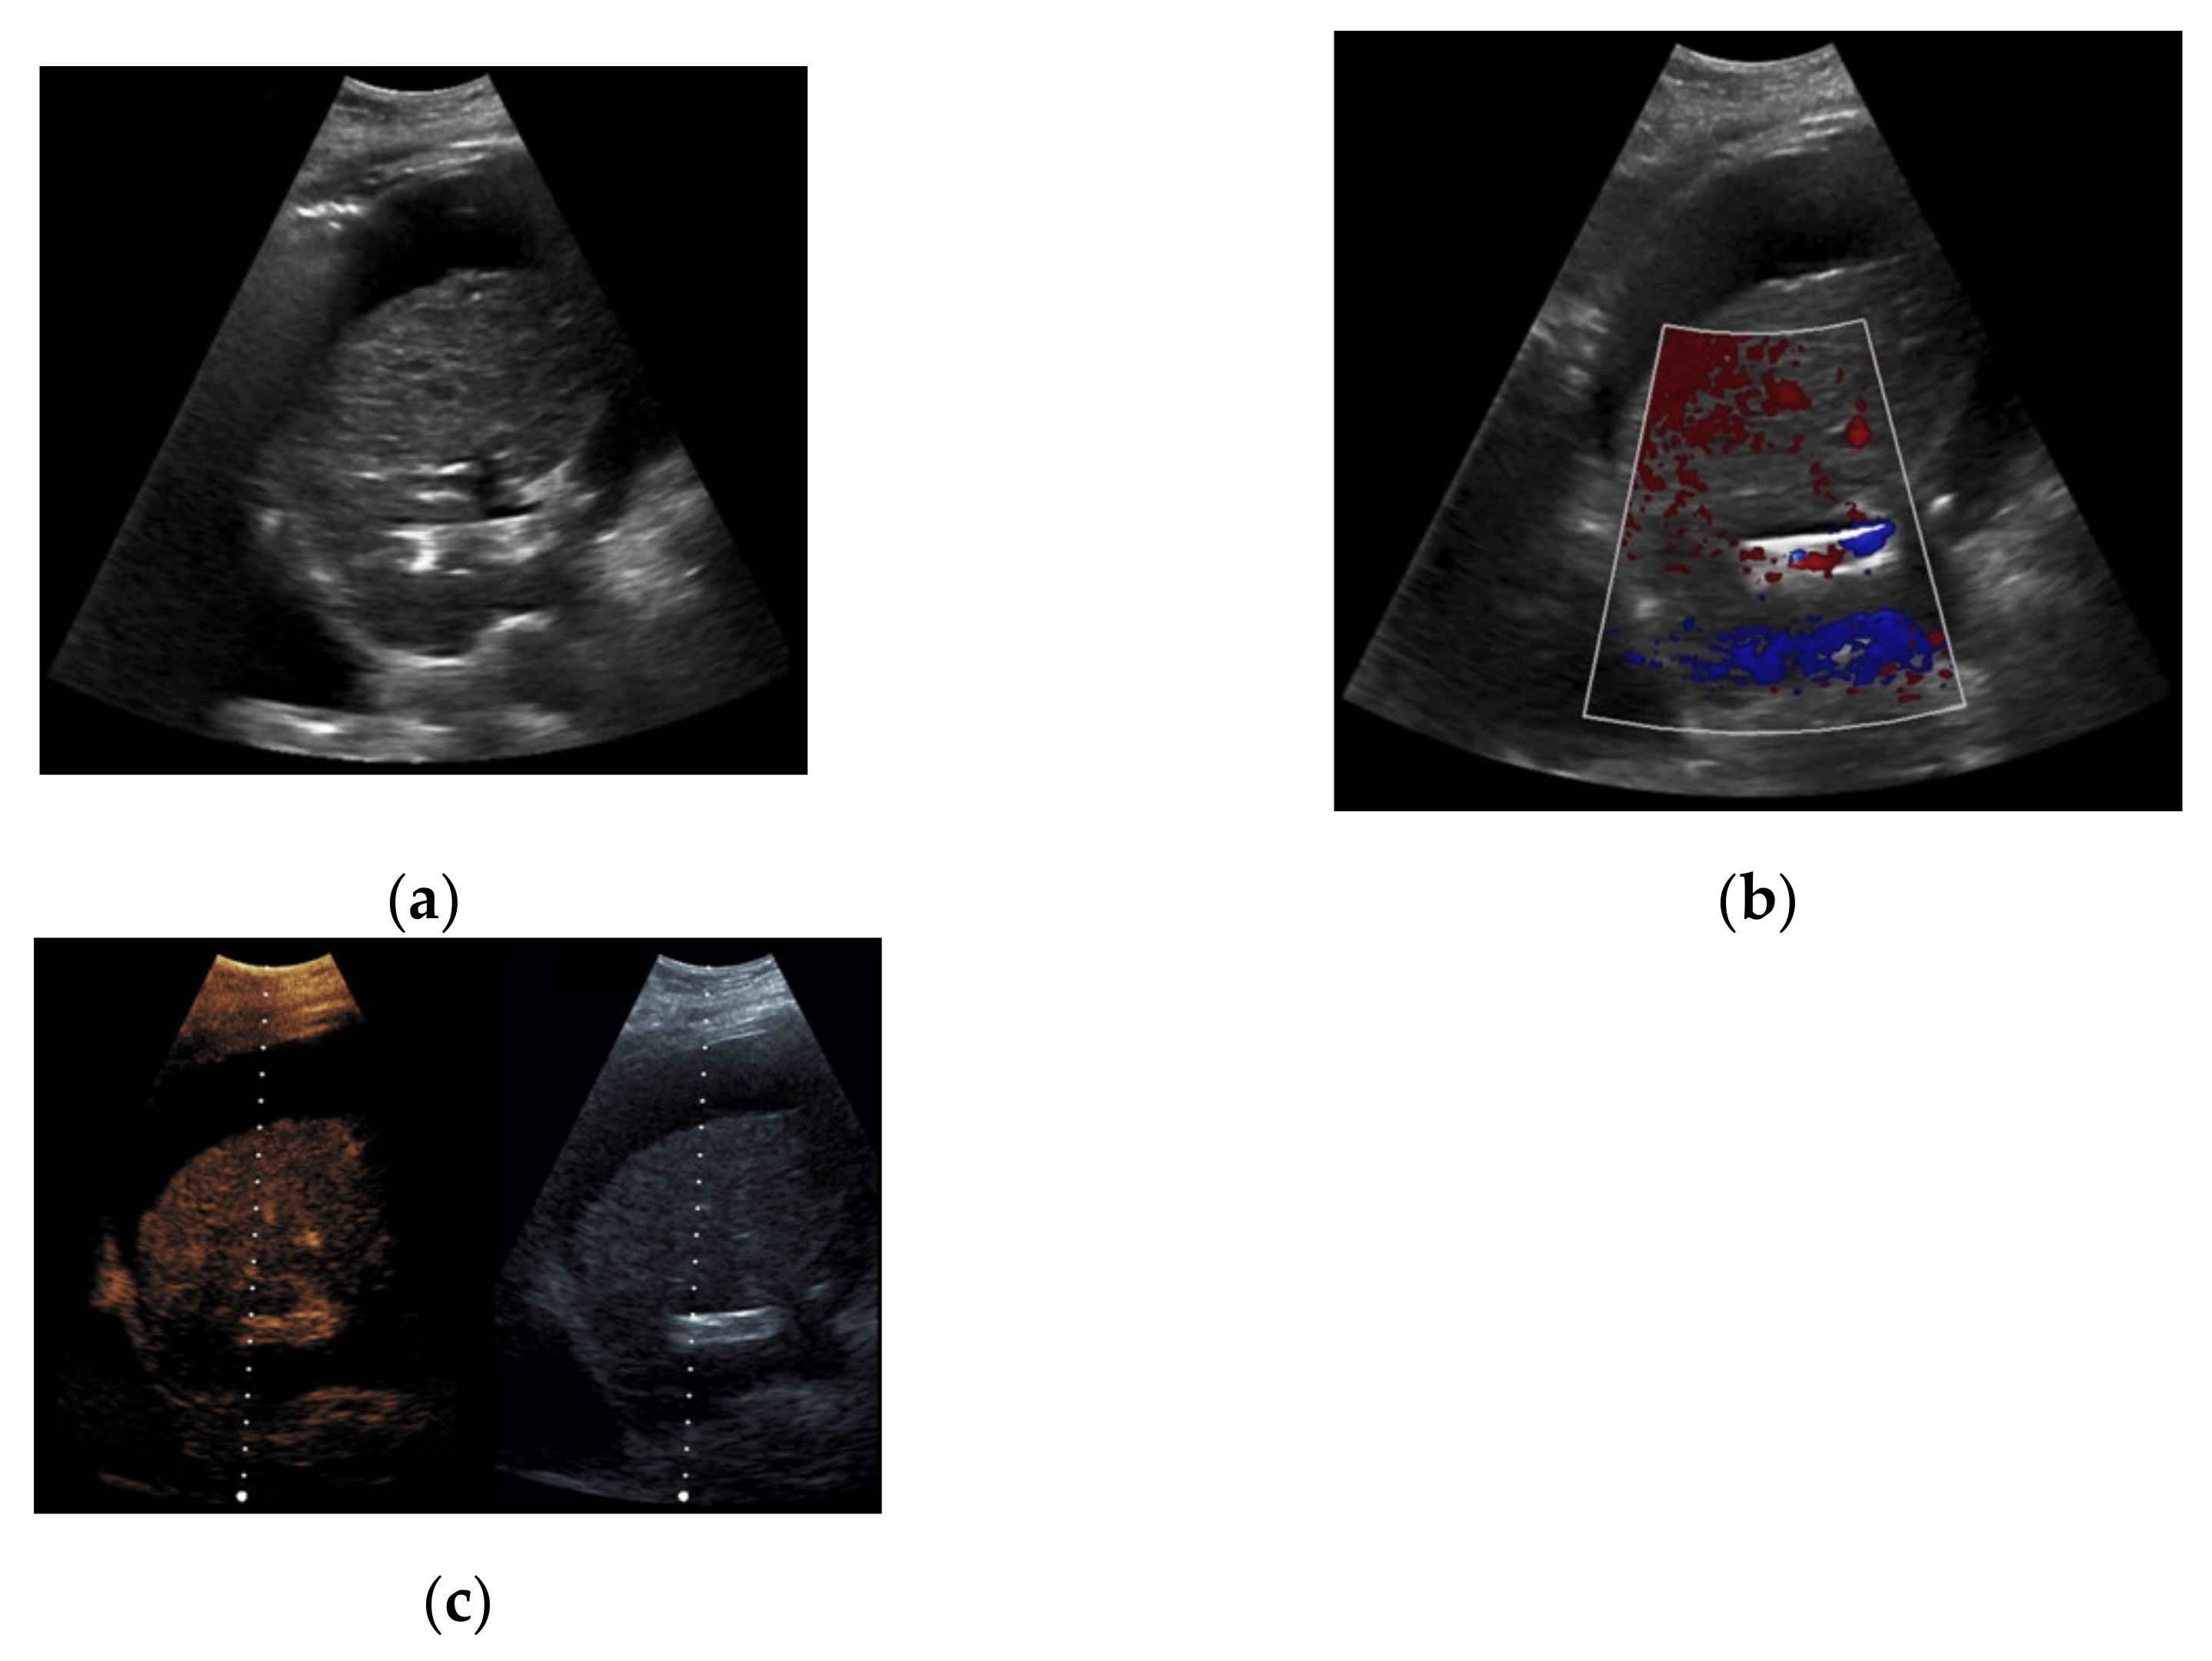

Figure 3. 44-year-old female patient with inhomogeneous flow signal on Color Doppler ultrasound as a sign of stent thrombosis.

Figure 4. Same patient as in Figure 1 with continuous flow within the transjugular intrahepatic portosystemic shunt (TIPS) without thrombosis or occlusion using microflow imaging (a) and after administration of contrast agent (b,c).